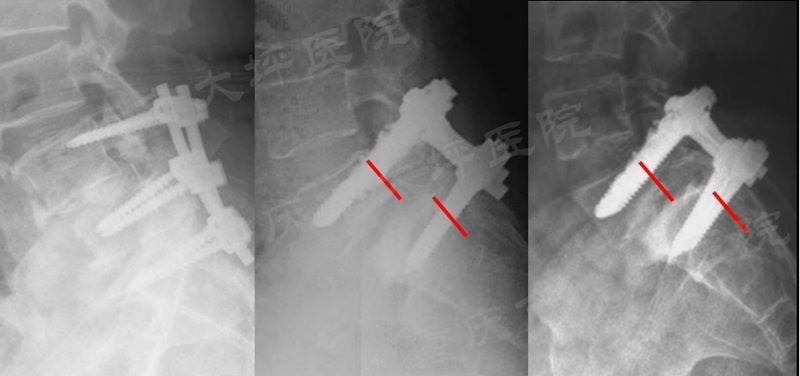

腰椎滑脱症是一种上位椎体相对于下位椎体向前滑移,以腰腿痛、间歇性跛行为主要症状的常见退变性脊柱疾病,成年人发病率约为6%。对于保守治疗无效的患者,采用后路椎弓根螺钉内固定技术复位滑移椎体、恢复腰椎序列、坚强固定达到骨融合是主要的治疗方式。然而,老年骨质疏松人群由于骨质疏松极大的降低了椎弓根螺钉的稳定性,极易发生内固定失败(图1)。

图1 腰椎滑脱内固定失败病例

课题组前期的回顾性病例对照研究证实,单侧使用PMMA螺钉(2颗)与双侧使用PMMA螺钉(4颗)具有相近的临床疗效,成功将PMMA螺钉使用的推荐数量从4颗减少为2颗。进一步观察发现,普通椎弓根螺钉失效模式为“雨刮效应”(图2)。

图2 CT扫描示意“雨刮效应”

骨水泥增强椎弓根螺钉后,由于骨-钉界面的应力分布特征被人为改变,失效模式与普通螺钉相比也发生了变化,将其称为“反雨刮效应”(图3),该现象的生物力学机制尚不清楚。课题组敏锐的发现,在其背后可能蕴含着合理应用PMMA螺钉的关键线索。

图3 “反雨刮效应”示意图